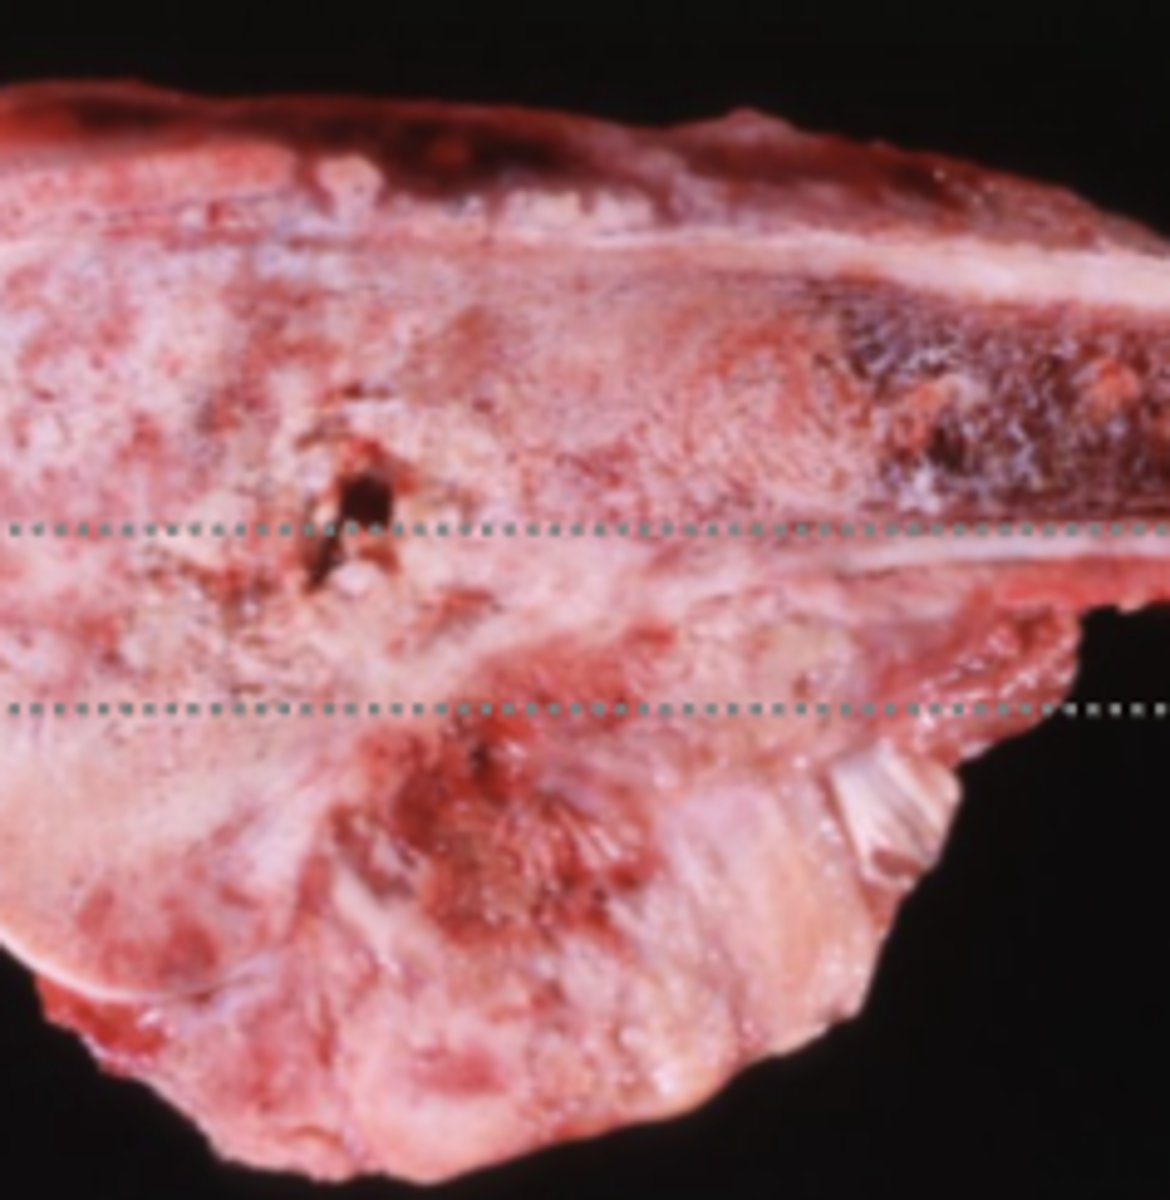

Hepatocellular carcinoma

-firm tissue

-malignant

-

What has caused this gross appearance of this liver?

Hepatocellular carcinoma

What has caused this gross appearance of this liver?